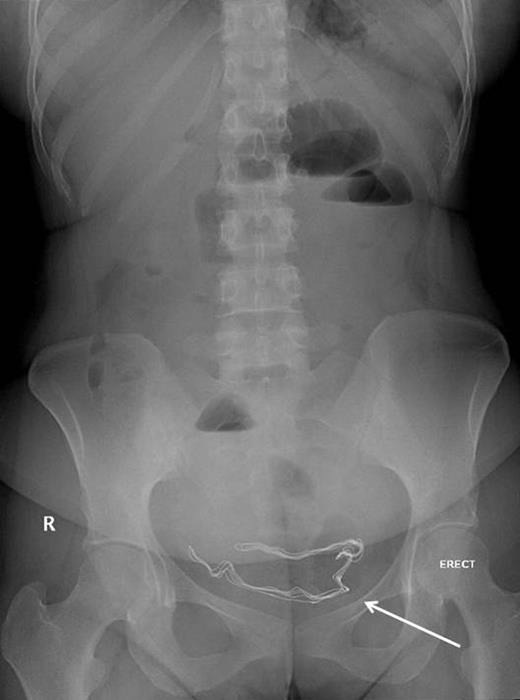

Upon admission, she was afebrile, vitally stable, and her abdomen was distended and tympanic. Bowel sounds were increased in frequency and pitch. Digital rectal examination showed normal-colored stool. Laboratory investigations showed a white blood cell count of 10 700 cells/ml and a sodium level of 123 mmol/l, while other biochemical parameters were within normal limits. Abdominal roentography revealed dilated small intestinal loops with a finding of a radio-opaque density in the abdomen (Fig. 2). A diagnosis of small intestinal obstruction most likely caused by retained surgical sponge was made. On abdominal exploration, the small intestine was dilated down to the ileum with an intraluminal mobile mass felt in the distal ileum (Fig. 3). Before proceeding for mass removal, at around 80 cm from the duodenojejunal junction, there were two adjacent segments of the jejunum adherent to each other and both were adherent to the peritoneal wall by fibrous adhesions. Consequently, adhenolysis, enterotomy and removal of the mass, which was manually pushed there (Fig. 4), followed by resection and anastomosis of the compromised jejunal segment, were achieved. The foreign body was found to be retained surgical sponge (Fig. 5). However, apart from the isolated area of adhesion, exploration of the rest of the abdominal cavity did not show any lesions in the peritoneal cavity or perforation or fistula or pelvic collection. The authors concluded that the transluminal migration of the sponge most likely occurred from that adherent part of the jejunum. The postoperative period was uneventful and the patient was discharged on the seventh day of her hospitalization in good condition.

Proximal small intestinal dilatation with the radio-opaque mark migrated proximally to the abdomen (arrow), indicating its mobile nature.